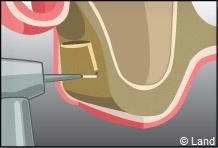

L’intervention est réalisée sous anesthésie locale. Dans cet exemple le forage intéresse la paroi latérale du sinus.

Une fenêtre est délimitée et réclinée à l’intérieur du sinus de manière à aménager un espace. Cet espace est rempli par le matériau de comblement qui peut être recouvert par une membrane.